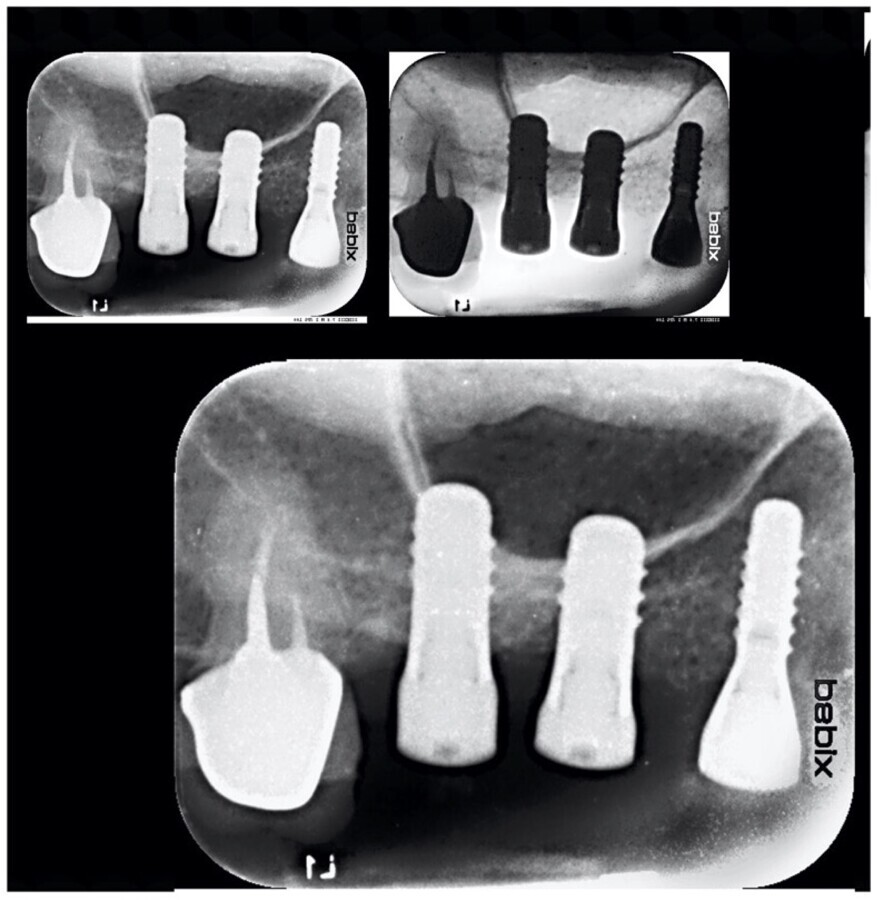

Figura 2. Imagen del control realizado a los 7 días.

Figura 3. El control a los 15 días muestra buena evolución.

Figura 4. La mejora continúa en este control realizado a los 3 meses.

Figura 6. La paciente muestra una buena osteointegración de los implantes en este control radiográfico realizado a los 30 meses.